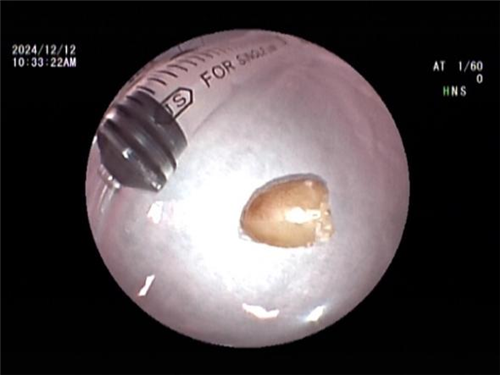

王海龙主任迅速组织团队对孟某展开全面综合评估,结合患者症状及各项检查结果,高度怀疑其患有吸入性气管异物并由此引发阻塞性肺炎。在与孟某及其家属进行充分且细致的沟通交流后,王海龙主任决定亲自为患者实施电子支气管镜检查。在支气管镜深入探查过程中,清晰可见患者右中叶支气管被一异物牢牢阻塞管腔。此异物表面光滑,质地极为脆弱,不仅易碎,还容易软化变形,这一系列棘手问题使得异物取出难度呈指数级增加。手术过程中,任何细微的失误都可能导致异物掉落至气管深部,从而引发更为严重且复杂的后果。但王海龙主任凭借其精湛高超的医术与沉稳冷静的临场应变能力,运用异物钳小心翼翼地进行操作,经过多次精准尝试,最终成功取出一枚长径约 1cm 的异物。术后,孟某的呼吸即刻恢复通畅,经过 5 天系统且精心的治疗,咳嗽、咳痰症状显著缓解,胸闷、气促等不适症状全然消失,肺部感染病灶也得到明显吸收。经确认,此次引发孟某一系列病痛的 “罪魁祸首” 竟是一粒花生米。